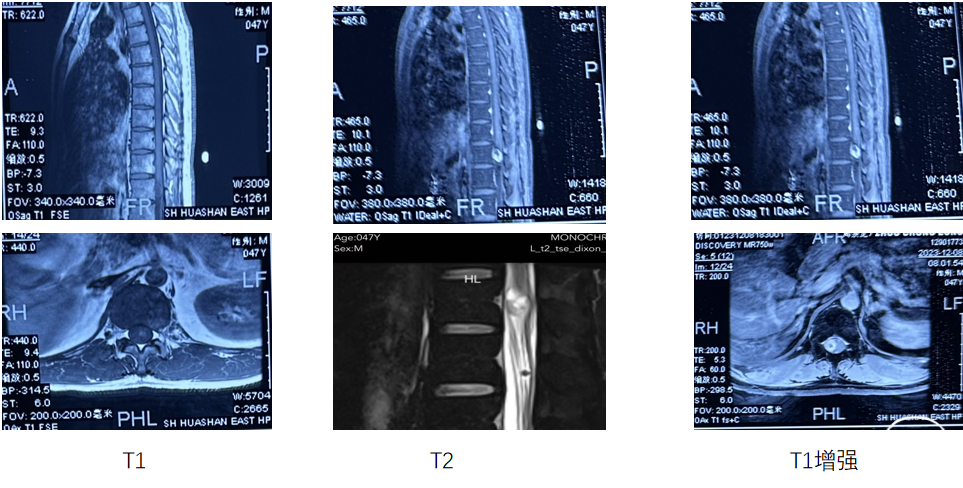

术前检查(胸椎及腰椎MR平扫+增强)

术前诊断:椎管内占位性病变(胸12节段?神经鞘瘤?)

手术计划:显微镜微通道下椎管内肿瘤切除术。

胸椎MR增强,本院,2024.04.24

术前诊断:椎管内占位性病变(胸9节段,神经鞘瘤?)